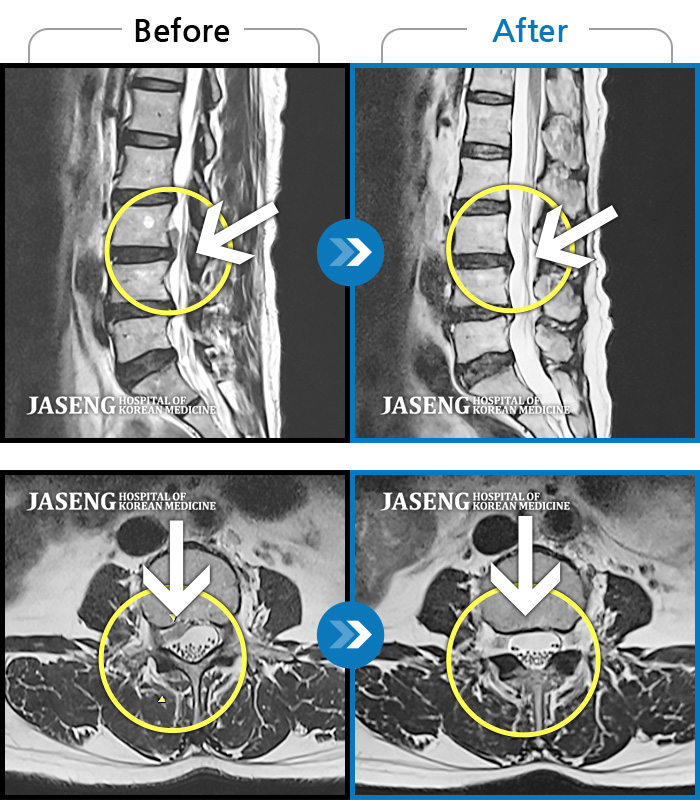

MRI 치료사례

허리 통증으로 내원